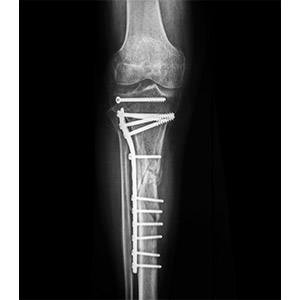

Traumatic Limb Salvage Surgery

Limb salvage surgery, also called limb-sparing surgery, is a surgical procedure that involves debridement- removal of the injured bone and surrounding tissues and reconstructing them into a functional limb. This may be done using an allograft, a bone graft from donor, metal implant, or a combination of metal implant and bone graft called allograft-prosthetic composite.